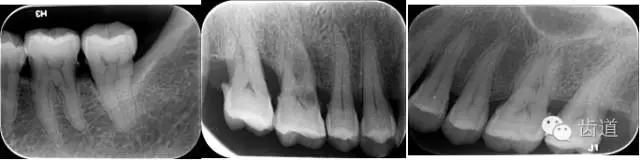

X線:根尖片、曲面斷層片(牙槽嵴頂,水平垂直吸收,程度)

21.webp.jpg

22.webp.jpg

23.webp.jpg